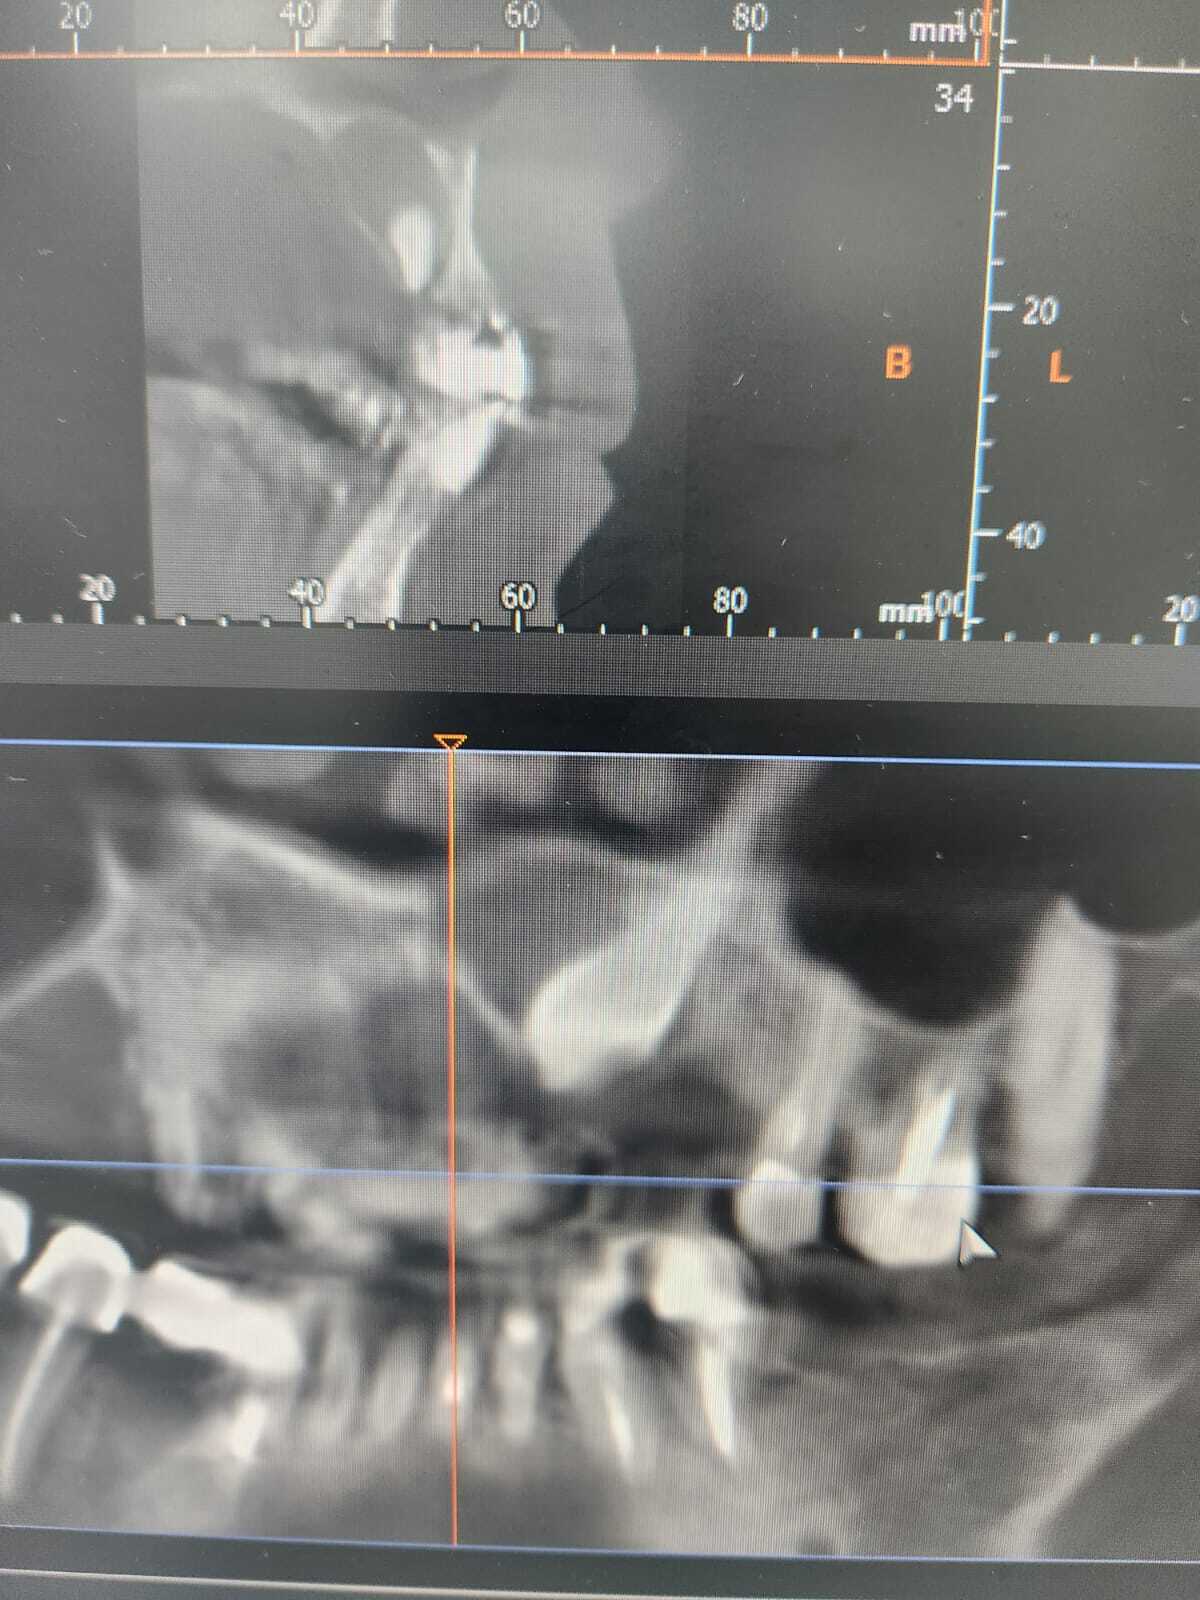

Доброго времени суток, пикабушники! Очень нужна ваша информационная помощь. Мне требуется операция на верхней челюсти - лежит ретинированный клык с приличного размера кистой, которая практически разъела всю кость под носом(( Где хорошие челюстно-лицевые хирурги работают? Территориально нахожусь в Воронеже, но рассматриваю ещё СПб или Москву.

Месяц назад узнала о кисте, места от страха не нахожу((